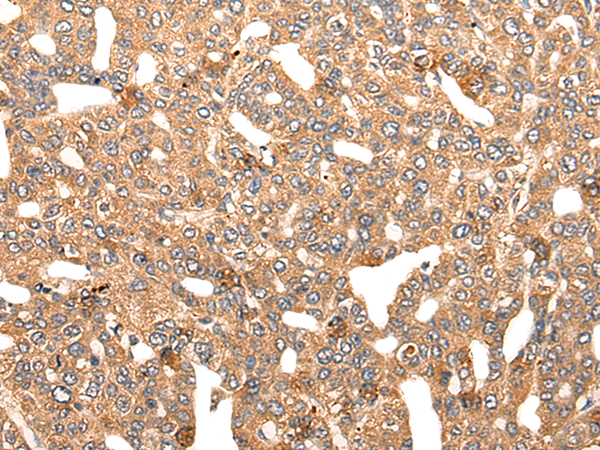

分类: 科研抗体货号: P13200别名: CLL1; MICL; CD371; CLL-1; DCAL-2应用: IHC反应种属: Human